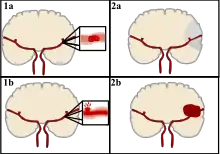

| CT scan of the brain showing a prior right-sided ischemic stroke from blockage of an artery. Changes on a CT may not be visible early on.[1] | |

The main risk factor for stroke is high blood pressure.[6] Other risk factors include tobacco smoking, obesity, high blood cholesterol, diabetes mellitus, a previous TIA, end-stage kidney disease, and atrial fibrillation.[2][6][7] An ischemic stroke is typically caused by blockage of a blood vessel, though there are also less common causes.[12][13][14] A hemorrhagic stroke is caused by either bleeding directly into the brain or into the space between the brain's membranes.[12][15] Bleeding may occur due to a ruptured brain aneurysm.[12] Diagnosis is typically based on a physical exam and supported by medical imaging such as a CT scan or MRI scan.[8] A CT scan can rule out bleeding, but may not necessarily rule out ischemia, which early on typically does not show up on a CT scan.[9] Other tests such as an electrocardiogram (ECG) and blood tests are done to determine risk factors and rule out other possible causes.[8] Low blood sugar may cause similar symptoms.[8]

CT scans may not detect an ischemic stroke, especially if it is small, of recent onset, or in the brainstem or cerebellum areas. A CT scan is more to rule out certain stroke mimics and detect bleeding.[9]